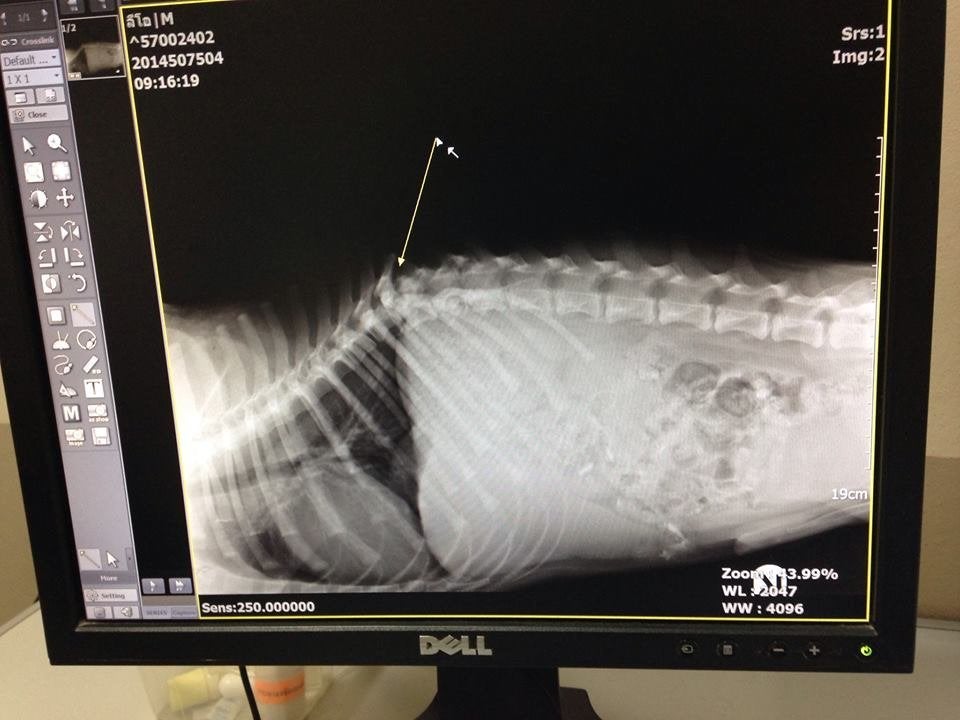

"I wasn't too surprised when I saw Leo's X-rays," the post read. "His back is broken and is completely paralyzed in his back two legs and feels no pain whatsoever in the lower half of his body. He will never walk again but then again I think we all knew that. He is still COVERED in ticks. Like thousands...but they should die off within the next week."